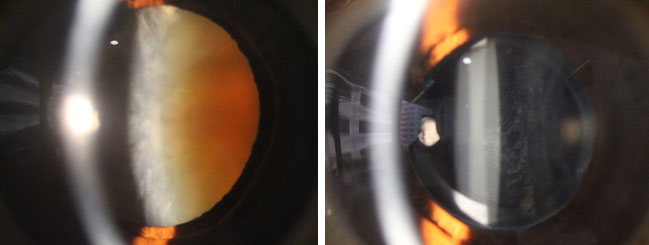

白內障手術前(左圖) 和後 (右圖)

白內障是指眼球內的晶體混濁,導致視力不清,情況就如一部相機的鏡頭受損,不能拍出清晰的照片。如要改善視力,必須把渾濁液晶體清除,再植入-片人工晶片,藉着個人化的人工晶片選擇,不但能改善視力,更能達致減少近視、遠視、散光,以致治療老化的效果。

眼科專科鄧維達醫生表示,現今的白內障手術,傷口較以往的手術大大縮小,以微創手術方式使用超聲波乳化技術,將混濁的晶體清除,再經由可捲曲的人工晶片植入眼內,手術便告完成。手術一般10至15分鐘左右,大部份可於表層局部麻醉(topical anaesthesia) 的方式進行,大多不需縫針或進行注射,讓手術過程更舒適快捷。